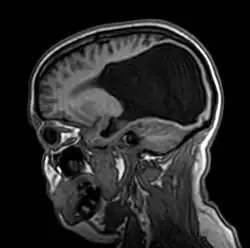

Colpocefalia

A colpocefalia é um trastorno no qual se evidencia um crescimento anormal dos sulcos ocipitais - a porção posterior dos ventrículos laterais (as cavidades ou compartimentos) do cérebro. Este crescimento anormal ocorre quando ocorre um subdesenvolvimento ou uma falta de espessamento na substância branca do cérebro posterior. A microcefalia (cabeça anormalmente pequena) e o retardo mental são característicos de uma colpocefalia. Outras condições incluem anormalidades motoras, espasmos musculares e convulsões. Ainda que a causa seja desconhecida, os pesquisadores acham que o trastorno resulta de um problema intrauterino que ocorre entre o segundo e sexto mês de gravidez. A colpocefalia pode-se diagnosticar numa fase avançada da gravidez, ainda que com freqüência se diagnostica erroneamente como hidrocefalia (um acúmulo excessivo do líquido cerebroespinhal no cérebro). Pode ser diagnosticada mais exatamente após o nascimento quando se evidenciam mostras de atraso mental, microcefalia e convulsões. Não há tratamento definitivo para a colpocefalia. Medicamentos anticonvulsivos podem-se administrar para prevenir convulsões e os médicos costumam prevenir contraturas (a contração ou encurtamento dos músculos). O prognóstico para os indivíduos com colpocefalia depende da gravidade das condições associadas e do grau de desenvolvimento anormal do cérebro. A educação especial pode beneficiar a alguns meninos.